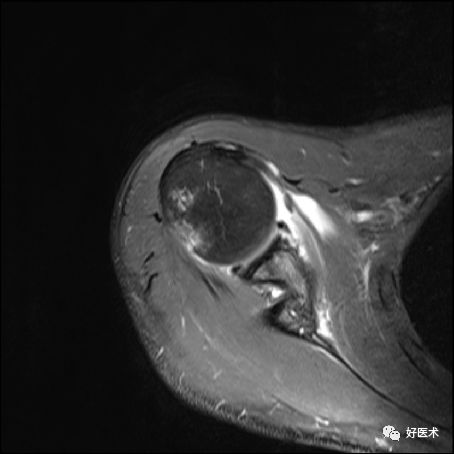

Bankart损伤的MR表现

-

三角形变钝

盂唇撕裂:关节盂唇软骨与盂缘可见线状高信号影并连续到关节面下

盂唇完全消失或盂唇明显移位

若盂唇损伤合并关节盂骨质损伤,称为骨性Bankart病变